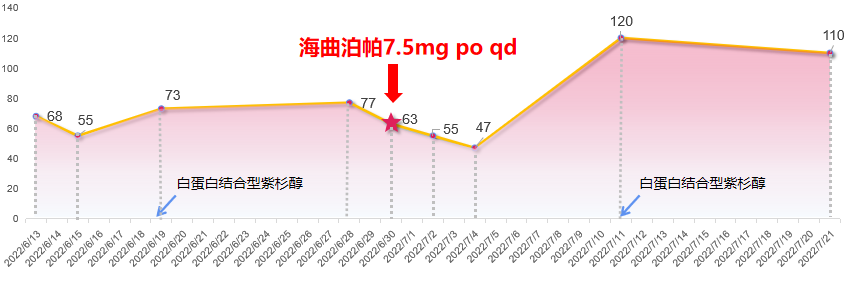

患者第1周期化疗结束后再次出现II度骨髓抑制,血小板降至63×109/L,予海曲泊帕7.5mg/天进行院外治疗,11天后患者返院,复查血常规升至120×109/L,顺利完成第2周期化疗。

本例患者确诊食管胃结合部腺癌Ⅳ期,HER-2阴性,基于指南推荐以及循证证据,给予化疗联合免疫治疗一线治疗7周期,复查CT提示疾病进展,故联合放疗。在三种抗肿瘤治疗方式的联合作用下,患者出现CTIT,血小板下降至75×109/L。给予rhIL-11治疗10天疗效欠佳,血小板持续下降,且出现下肢水肿不良反应,改为rhTPO治疗7天后血小板降低得以改善。然而随着治疗周期的增加,患者在下一周期出现了更为严重的血小板减少症,血小板降至38×109/L,遂予以新一代血小板生成素受体激动剂(TPO-RA)海曲泊帕联合rhTPO治疗,血小板快速回升,保证患者按时按量的完成抗肿瘤治疗。此后患者复查CT再次提示疾病进展,重新评估病情后予白蛋白紫杉醇单药化疗,化疗过程中再次出现血小板下降。考虑rhTPO针剂注射治疗需住院或频繁返院,增加相关治疗成本,因此给予患者海曲泊帕7.5mg/天行院外治疗,有效且便捷地提升血小板,使患者顺利完成后续治疗。